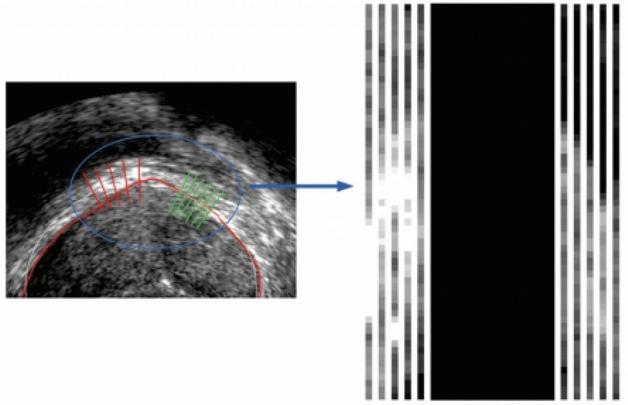

一种语义约束下的前列腺超声图像双向分割方法。

A bi-directional segmentation method for prostate ultrasound images under semantic constraints.

Due to the lack of sufficient labeled data for the prostate and the extensive and complex semantic information in ultrasound images, accurately and quickly segmenting the prostate in transrectal ultrasound (TRUS) images remains a challenging task. In this context, this paper proposes a solution for TRUS image segmentation using an end-to-end bidirectional semantic constraint method, namely the BiSeC model. The experimental results show that compared with classic or popular deep learning methods, this method has better segmentation performance, with the Dice Similarity Coefficient (DSC) of 96.74% and the Intersection over Union (IoU) of 93.71%. Our model achieves a good balance between actual boundaries and noise areas, reducing costs while ensuring the accuracy and speed of segmentation.

摘要

由于前列腺缺乏足够的标注数据,且超声图像中的语义信息广泛而复杂,在经直肠超声(TRUS)图像中准确、快速地分割前列腺仍然是一项具有挑战性的任务。在此背景下,本文提出了一种使用端到端双向语义约束方法的TRUS图像分割解决方案,即BiSeC模型。实验结果表明,与经典或流行的深度学习方法相比,该方法具有更好的分割性能,骰子相似系数(DSC)为96.74%,交并比(IoU)为93.71%。我们的模型在实际边界和噪声区域之间实现了良好的平衡,在确保分割准确性和速度的同时降低了成本。